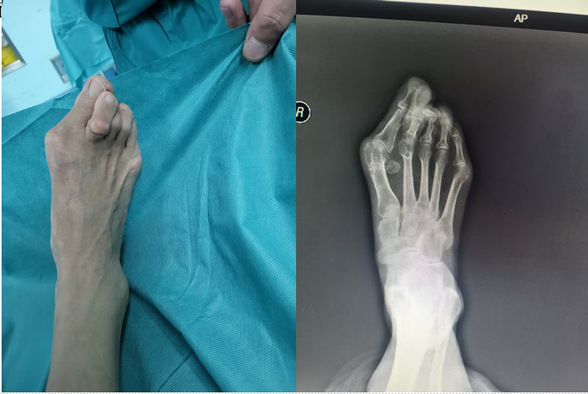

传统拇外翻术前

传统拇外翻术后

这三位患者均为足拇趾外翻多年,随着年龄增长,外翻的程度越来越严重,穿鞋困难、疼痛难忍,已严重影响到日常生活,于是来到我院骨外四科就诊。在骨外科主任邢星的带领下,经过术前病情分析和讨论,周密检查,决定行微创拇外翻技术治疗。在麻醉科与手术室的密切配合下,顺利完成手术。术中仅1个不足1 厘米小切口,患者患足术后外观恢复满意。拇外翻(俗称“大脚骨”),总体发病率为10%—20%,女性占比远高于男性。

拇外翻角(HVA)大于15°,跖间角(IMS)大于10°,结合临床表现就可以判断拇外翻,生活质量下降。传统拇外翻手术往往需要较大的切口和复杂的内固定操作,术后恢复周期长且伴有一定的痛苦,邢星主任团队所采用的第三代拇外翻矫治技术,则以其微创特点,改变了这一现状,患者在接受手术后,足部畸形得到即时纠正,外观更加美观自然,避免了二次手术取内固定的繁琐与痛苦。目前第三代拇外翻微创手术已得到国际足踝外科学会(IFFAS)、美国足踝外科学会(AOFAS)等权威机构认证。